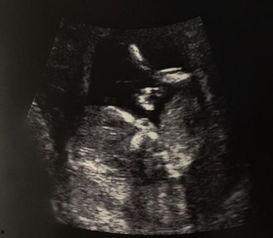

自从明星宣布怀孕的消息传出来后,B超照片就成了大家关注的焦点。这不,明星在微博上晒出了自己的B超照片,照片中,宝宝的小手和小脚都清晰可见,让人忍不住想要亲一口。网友们纷纷留言:“哇,好可爱啊!”“恭喜恭喜,宝宝健康就好!”“期待宝宝的到来!”

在娱乐圈,明星们对于宝宝的性别总是格外关注。而B超,就是他们了解宝宝性别的重要途径。据专家介绍,B超检查宝宝性别的时间一般在怀孕18周到24周之间,这时候宝宝的大小适中,性别特征比较明显。而明星们晒出的B超照片,也让我们看到了宝宝性别的神秘面纱。